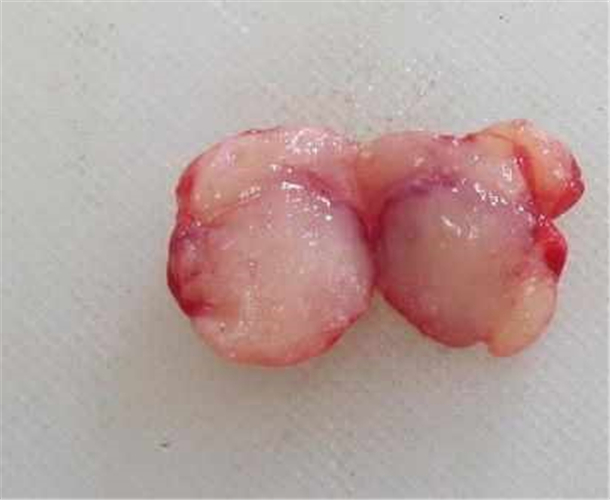

纤维瘤乳腺图片

乳腺纤维瘤

乳腺纤维瘤

乳腺纤维瘤

乳腺纤维瘤

乳腺纤维瘤